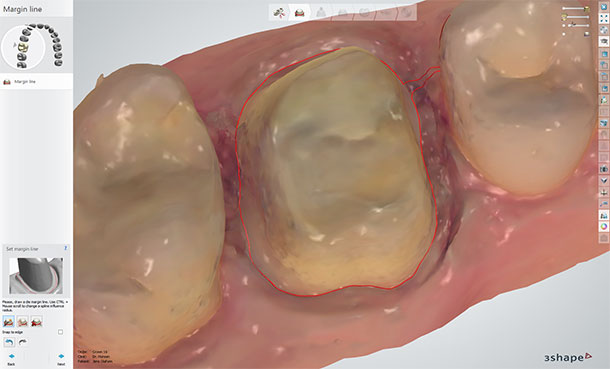

1.5 Set Margins

It's a good idea to combine viewing the impression with and without colors when setting the margin line. The two separate views will bring out different aspects of the margin area and help you determine the exact margin line position. You can also use HD photos if the dentist included these with the digital impression. The 2014 version of TRIOS software makes it easier than ever to see margin details. Here again, the dentist may have set a margin line, but its good practice for the lab to control this before designing and milling the crown.